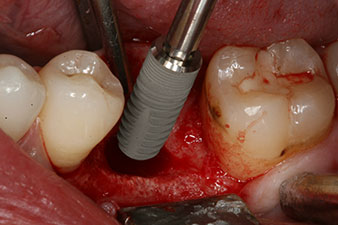

Implantat

Abb. 3: Nach Aufbereitung mit dem Implantmed Implantologiemotor wird ein Implantat (Durchmesser 4 mm, Länge 12 mm) bei einem Drehmoment von 43 Ncm maschinell eingeschraubt.

Nach gründlicher Entfernung des Granulationsgewebes wurde das Implantat wie geplant eingebracht (blueSky, bredent).

Das Drehmoment beim maschinellen Einbringen war 43 Ncm. Zusätzlich wurde, nach Einschrauben eines speziellen, auf das Implantatsystem abgestimmten Mess-Pfostens (SmartPeg), der ISQ-Wert mit der Sonde des W&H Osstell ISQ Modul bestimmt.